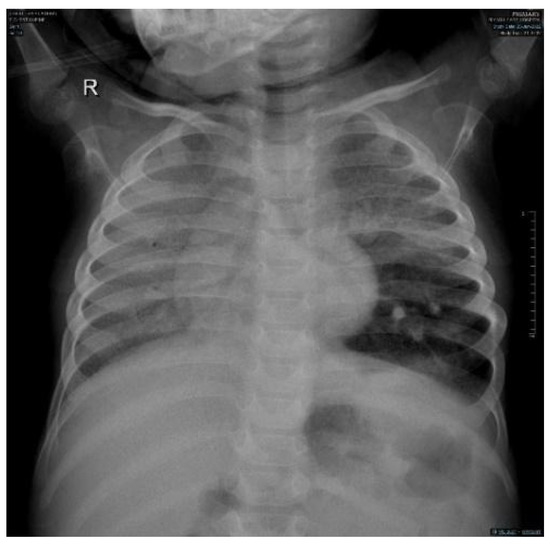

3.1. Chest X-ray

There were homogenous ground glass opacities involving the entire right lung and the left upper and middle zone with mesocardium due to mild rotation to the right side; there was some retrocardiac collapse and secondary hyperinflation of the left lower lobe but there was no attenuation of the blood vessels to suspect pulmonary emphysema as a possible sign of NPC2 (Figure 2).

Figure 2.

Chest X-ray anteroposterior film shows a diffuse right lung and left upper lobe ground glass opacity with retrocardiac collapse and hyperinflation of the left lower lobe but no oligemia. The mesocardium is explained by the mild rotation to the right side.

Niemann–Pick disease type C2 is predominantly respiratory, in contrast to NPC1 [7,8]. There are three types of pulmonary alveolar proteinosis (PAP): autoimmune (the most common), hereditary, and secondary PAP, and coexistence between NPD and PAP is well established in the literature [9,10]. The coexistence of NPD and PAP is the main presentation of NPC2, leading to respiratory failure [11,12]. Similarly, our patient presented with progressive respiratory insufficiency. Furthermore, the instillation of olive oil in his nostrils with possible lipoid pneumonia possibly worsened the respiratory status of our patient [13]. Moreover, the chest X-ray showed homogenous opacity involving the entire right lung and the upper and middle zones of the left lung with an air bronchogram, and the chest CT showed a ground glass appearance together with intrapulmonary fat infiltrate with a Hounsfield unit score of −40 HFU (−40 to −130) PAP [14,15]. Our case showed ground glass opacities, mild smooth interlobular septal thickening, and intralobular lines as a crazy-paving pattern that could suggest a diagnosis of NPD with no evidence of emphysematous lobe, which has been reported as a sign of NPC2 [16,17].